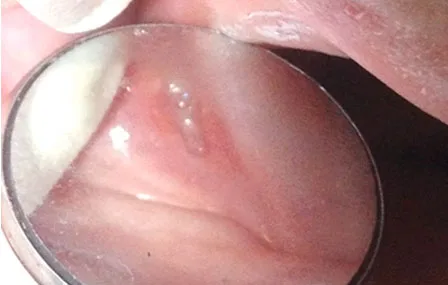

Incitation à la détection précoce - Lésions précancéreuses et cancéreuses, cavité buccale

Auteurs : S. DAKPE, C. NEIVA, B. LAPOTRE-LEDOUX, A. ALGRIN, A. CAULA, S. TESTELIN, B. DEVAUCHELLE Service d’épidémiologie et de…

Lire la suite →